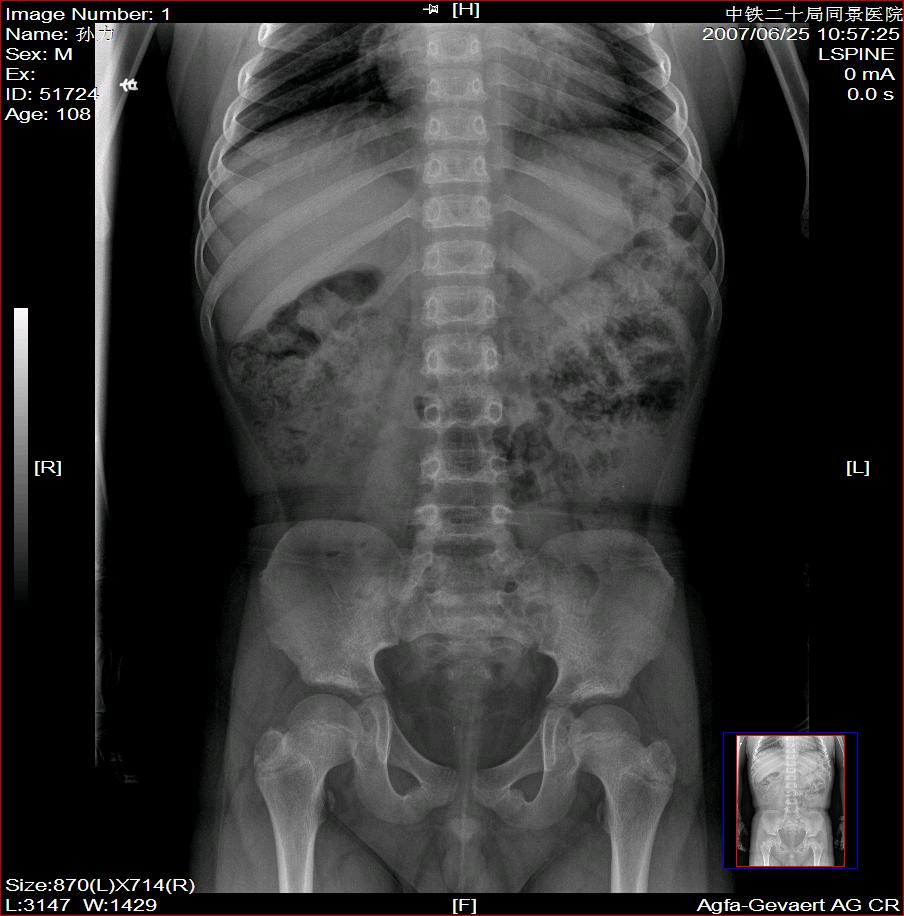

标题: X2504:M17Y,高中生,身高不足1.2米,智力正常 [打印本页]

标题: X2504:M17Y,高中生,身高不足1.2米,智力正常

年龄17岁,身材矮小(1.2m),全身骨骼发育迟缓,骨骺线仍较宽,但全身骨骼骨质正常,智力正常。

骨结构正常,骨骺线与17岁不符,豆状骨未见,相当7-8岁骨龄,结合智力正常,垂体性侏儒可能大。

考虑垂体侏儒的可能。依据1骨龄延迟,骨胳结构正常,智力正常。与甲状腺功能不足区别呆小症病人长骨及骨垢有改变,骨垢较正常小。椎体变扁。考虑垂体侏儒症。

各部比例在正常范围,为均称型侏儒,可见于1、垂体性侏儒。2、致密性骨发育不全。3、turner氏综合症。本例骨密度正常,皮质边界清,显然不支持致密性骨发育不全,未见掌骨征阳性和指骨优势,turner氏综合症,可基本除外,剩下的只有垂体性侏儒了,建议垂体mri进一步检查,确定诊断。以上主要参考曹来宾教授发表的论文,侏儒症的临床x线分析

全身骨骼发育迟缓,骨骺线仍较宽与年龄不符。考虑垂体性侏儒可能大。